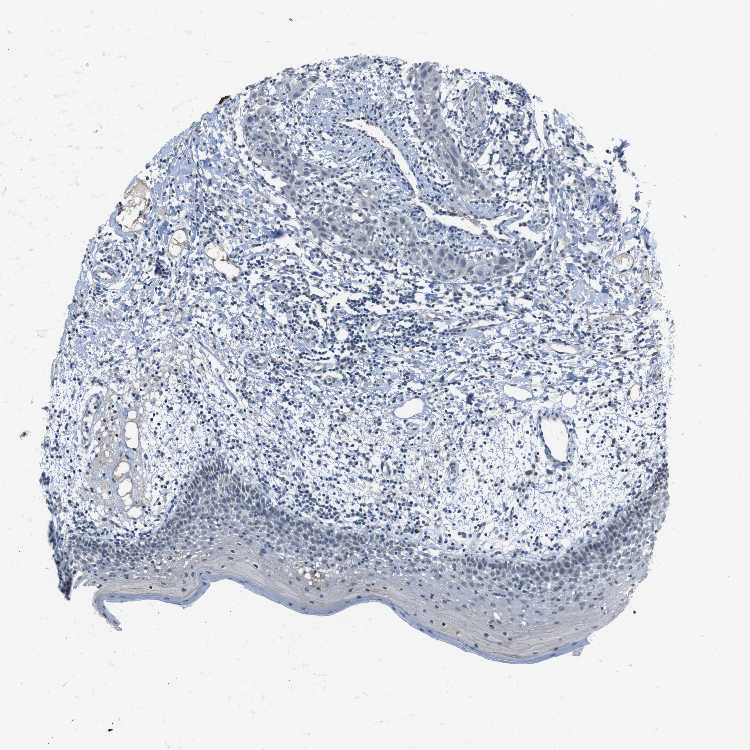

CDHR2